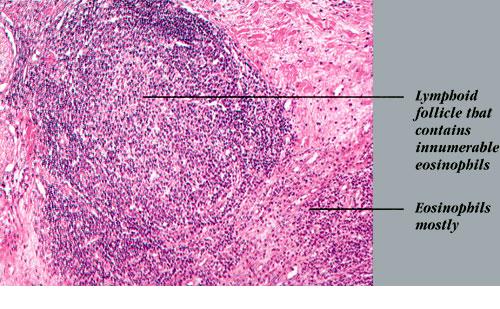

Histopathologically, the dermis and/or subcutis exhibit hyperplasia of small blood vessels lined by plump endothelial cells similar to those present in the high endothelial venules of lymphoid tissues. These venules are a major point of lymphocyte trafficking between the blood and the paracortical T-cell domain of lymph nodes. Surrounding these hyperplastic vessels is a dense infiltrate composed of small lymphocytes, plasma cells, histiocytes, and eosinophils. The latter are typically prominent but may be absent in some cases. There are usually multiple secondary lymphoid follicles with prominent germinal centers, particularly in the subcutaneous lesions. In general, lesions are more superficial and the vascular features are more prominent in AHLE, whereas lesions are deeper and the lymphoid features are more prominent in Kimura disease.